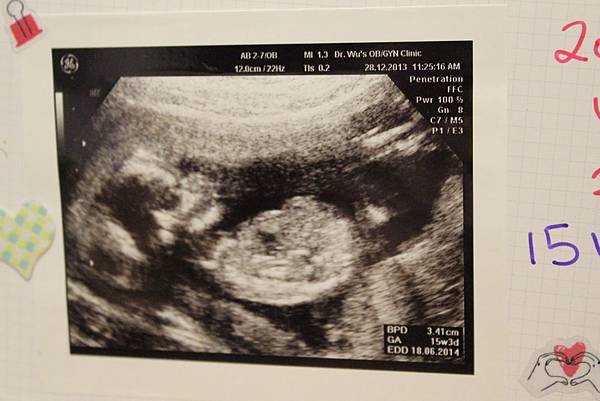

• 【孕期】小Abby的形狀出現了

IMG_3870.JPG

事隔一個多月後

又到了產檢的興奮日!